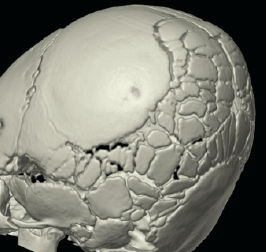

osteogenesis imperfecta

05/26/2015

A 5-week-old girl with an uncomplicated birth history presented to a pediatric emergency department with concern for swelling of her right leg. There had been no known traumatic event.